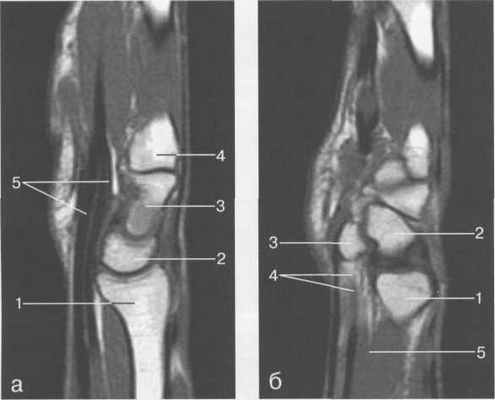

Рис. 19.55. MPT лучезапястного сустава в сагиттальной плоскости.

а — через плоскость лучевой кости: 1 — лучевая кость; 2 — полулунная кость; 3 — головчатая кость; 4 — основание II! пястной кости; 5 — сухожилие m. flexor digitorum profundus et superficialis. 6 — через плоскость гороховидной кости: 1 — лучевая кость; 2 — трехгранная кость; 3 — гороховидная кость; 4 — сухожилие m. flexor digitorum profundus et superficialis; 5 — т. pronator quadratus.